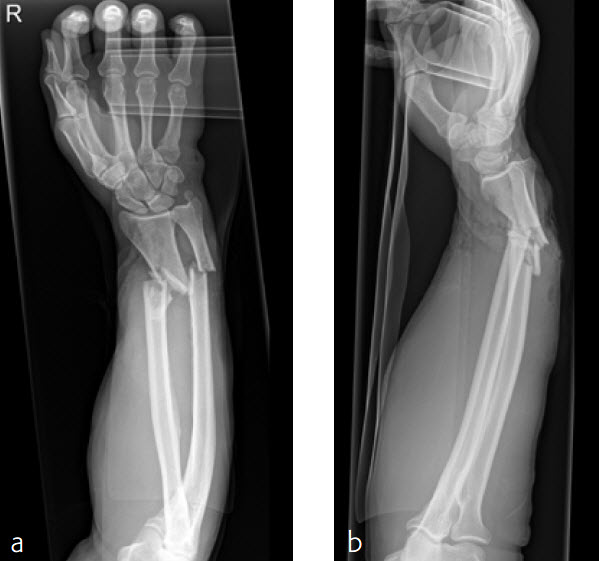

Case 4: Open radius shaft fracture

A 59-year-old farmer suffered a crush injury with an open forearm fracture (AO22 C2, Gustilo and Anderson IIIB) (Fig 1). Initial stabilization was carried out by external fixator (Fig 2). After four rounds of debridement and capillary ingrowth of a splitting skin graft at day 17, the VA LCP Extra Long Two-Column plate was used for fixation of the radius. A 2.7 mm LCP Condylar Plate was used for fixation of the ulna. The plates provided good stability for a functional after-treatment.

At the 3-month follow-up, the patient was full weight bearing with healing fractures (Fig 3).